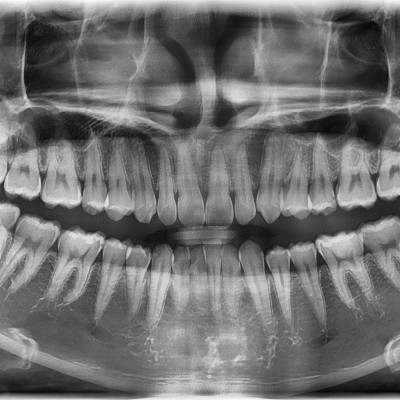

#18사랑니 발치 + #19 과잉치발치 #18사랑니 발치 + #19 과잉치발치 구강 외과 전문의가 당일 발치했습니다. ---------------..